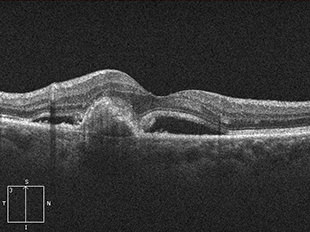

糖尿病黄斑浮腫

糖尿病黄斑浮腫は、糖尿病網膜症の合併症として発症します。網膜の細い血管に瘤ができてもろくなり、血管から血液中の成分がもれだし、それが網膜内にたまり浮腫(むくみ)を起こします。特に視機能において重要な部位である黄斑部に浮腫が生じると、ものが見えづらくなります。さらに浮腫が黄斑の中心部にまで及ぶと、著しい視力障害をきたし、かすんで見えたり、見えないところができたり、歪みが生じたりします。

治療前 OCT

治療後 OCT